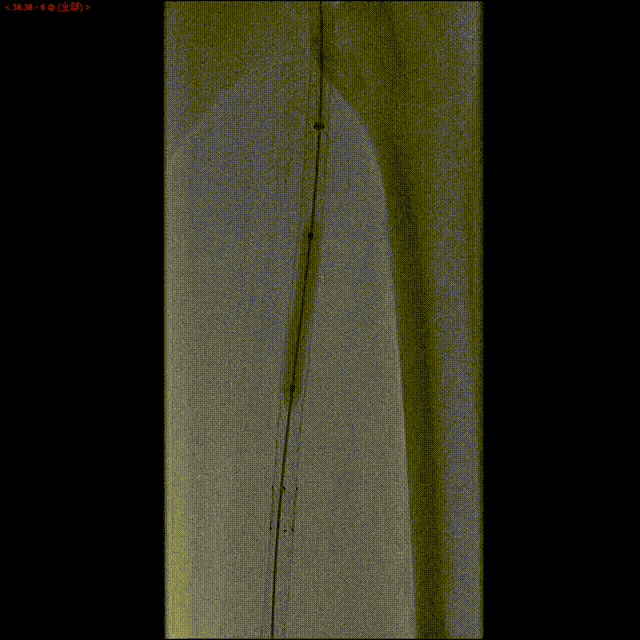

撤出正向微导管及逆向导丝,沿正向导丝置入直径为2.0 mm的准分子激光Turbo Elite导管扩大管腔以建立轨道,以能量40,频率40进行第一次激光消融;再以能量60,频率60进行第二次激光消蚀,消蚀4分28秒,发射脉冲12717次。

第一次激光消蚀(能量40,频率40)

第一次激光后造影

第二次激光后消蚀(能量60,频率60)

准分子激光消蚀后,进行球囊扩张,球扩后造影显示良好效果。

术后造影